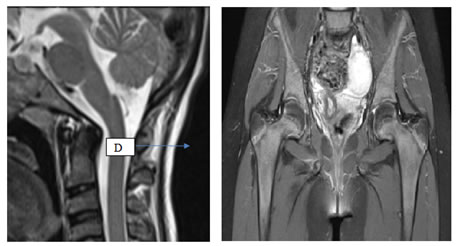

Figure 4: Figure 5:

Figure 4: MRI Cervical Spine Saggital T2WI sequence: Subtle clivus odontoid angulation with angulation of caudal portion of medulla oblongata and proximal portion of spinal cord.

Figure 5: MRI Bilateral Hip joint Proton Density Sequence Coronal View: